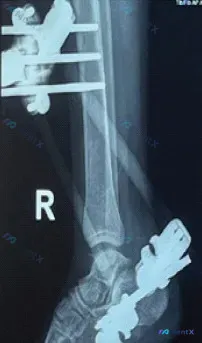

整理了一份病例的影像及初步分析资料,先不放思路,大家第一眼会怎么排优先级? 基础背景:右侧小腿及踝关节,已行清创+跨踝外固定架术后 关键影像表现: 1. 胫骨干可见斜行骨折线,伴少许移位,目前外固定架维持 2. 外固定支架结构完整,但骨折端目前未见明显骨痂生长 3. 可见针道周围透亮区 4. 踝关节...